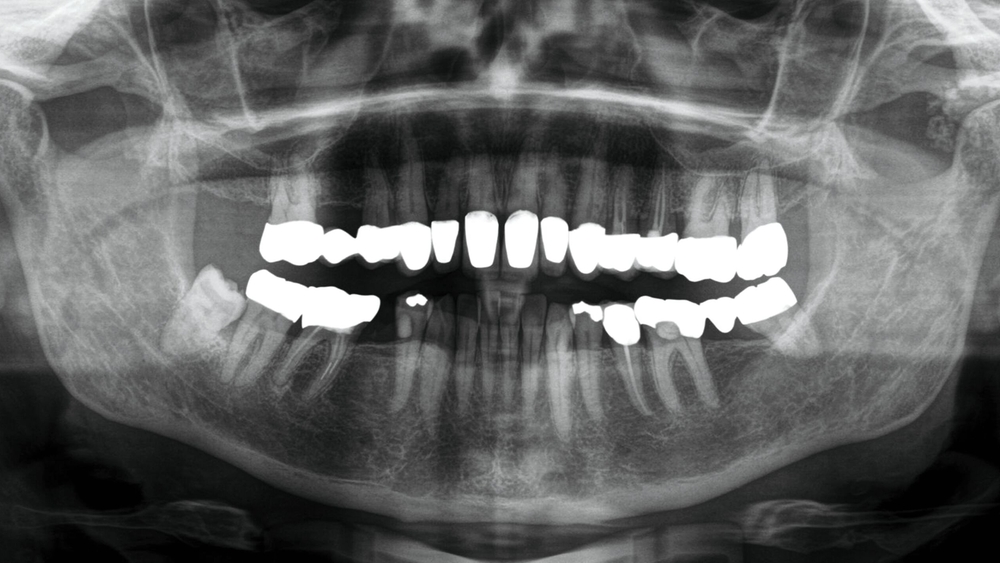

Eine 63-jährige Patientin stellte sich mit einem durch den Hauszahnarzt detektierten Zufallsbefund im linken Kiefergelenk vor. Aufgrund von Mundöffnungsstörungen hatte sie einen Monat zuvor dessen Praxis aufgesucht. Auf der in der Praxis angefertigten Panoramaschichtaufnahme (Abbildung 1) erkennt man opake, rundlich-strukturierte Raumforderungen über dem linken Kiefergelenk.

Nebenbefundlich berichtete die Frau über eine persistierende Müdigkeit, ein Schwächegefühl und Verspannungen der Nackenmuskulatur. Im Rahmen der weiteren differenzialdiagnostischen Abklärung durch den behandelnden Hausarzt wurde eine Polymyalgia rheumatica (Autoimmunerkrankung mit Vaskulitits) diagnostiziert und mittels Kortikosteroiden behandelt. In der Folge verschwanden auch die Beschwerden im Bereich des Kiefergelenks. Dennoch erfolgte aufgrund der Persistenz der Gelenkkörper eine Vorstellung an der Universitätsklinik.